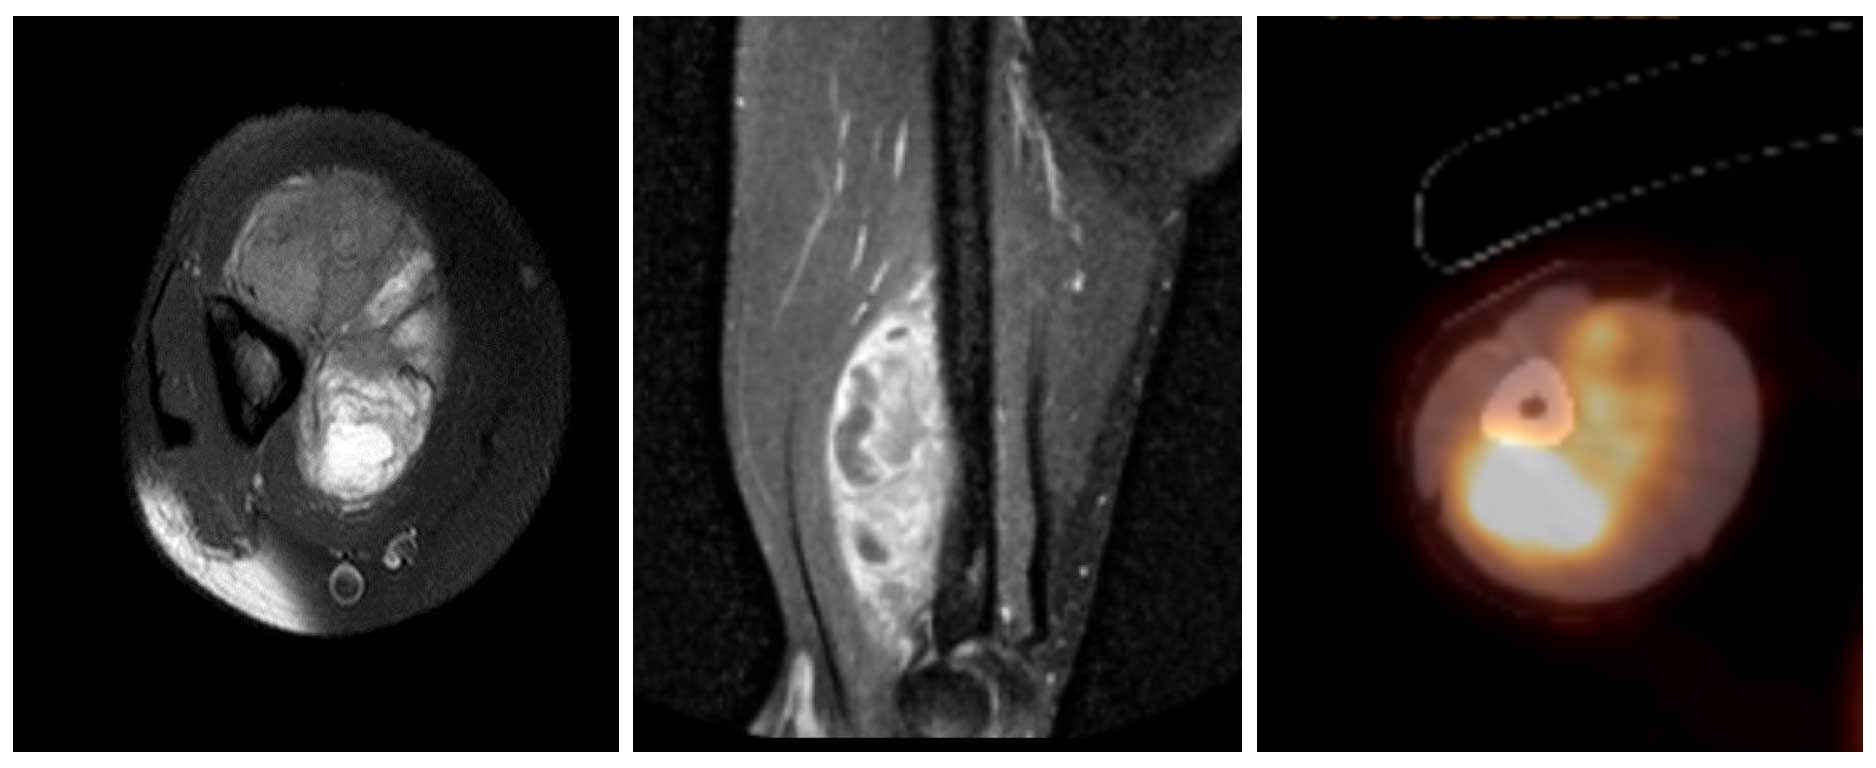

Ameliyat Öncesi: MR’da distal humerus anterior yerleşimli korteksde çökmeye neden olan heterojen yumuşak doku kitlesi, Pet-CT’de artmış aktivite görülmekte.